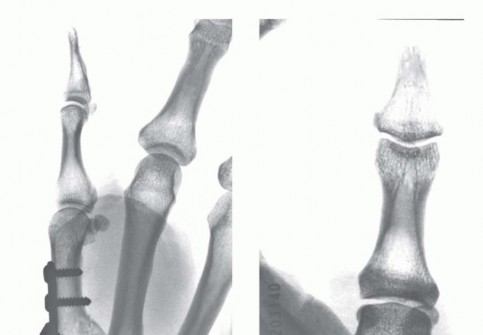

For a large fragment Bennett fracture, the shaft is reduced to the volar-ulnar fragment using a pointed reduction clamp. Provisional fixation is achieved with a K-wire. A 1.5mm or 2.0mm lag screw is then placed perpendicular to the fracture plane. The near cortex must be overdrilled (gliding hole) and the far cortex underdrilled (thread hole) to achieve true interfragmentary compression. The screw head should be countersunk to prevent hardware prominence beneath the thenar muscles.

Image